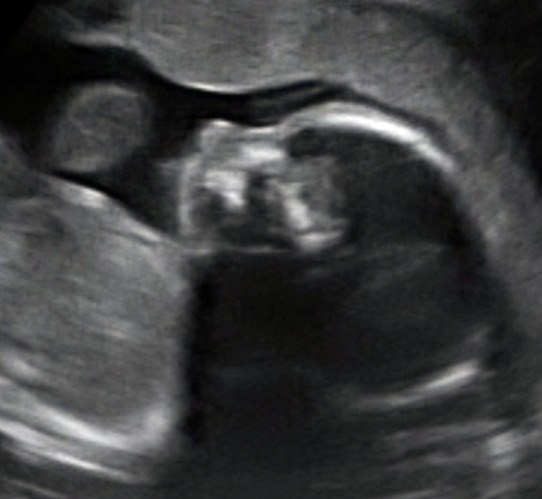

MAMA GRATULUJE KOCHANA!!!!!!!!!!!!

Strasznie sie ciesze! Teraz dbaj o siebie